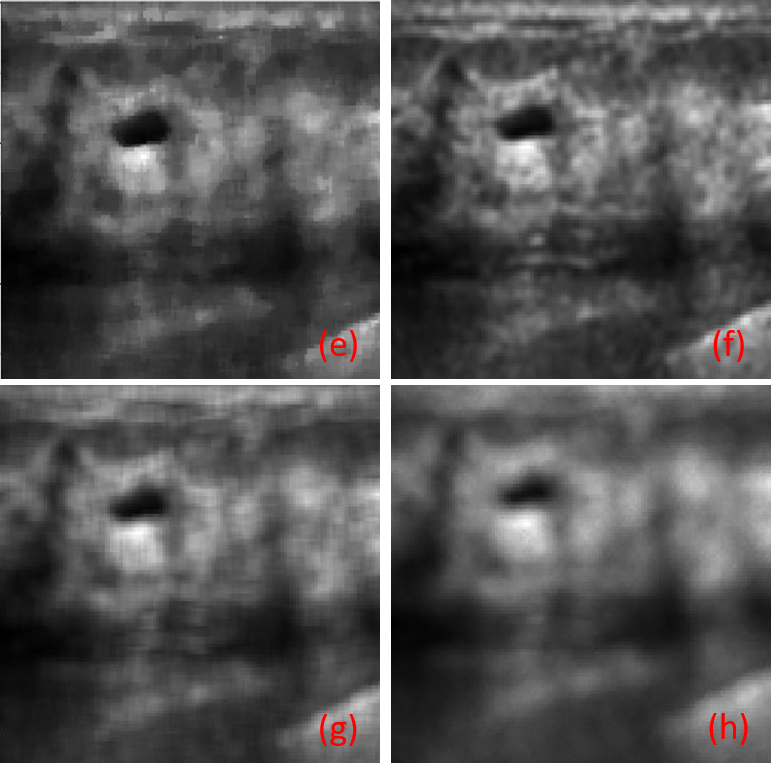

The results of the experimental study were compared in Table I. The results shown in dark color in the table correspond to the results obtained from the proposed denoising autoencoder with skip connections. As seen in the table, our proposed method yielded better results than other classical filters. The performance of the image denoising autoencoder with skip connections was evaluated using PSNR, SSIM, and MSE metrics. The network was trained with a noise variance of 0.7, resulting in a PSNR of 20.264, SSIM of 0.9, and MSE of 0.009. These results demonstrate the effectiveness of our proposed method when compared to other denoising techniques.